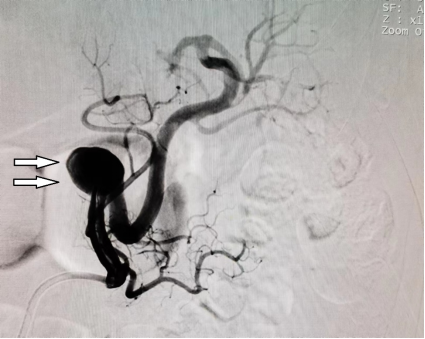

DSA造影显示动脉瘤情况,白箭头所指为瘤体。